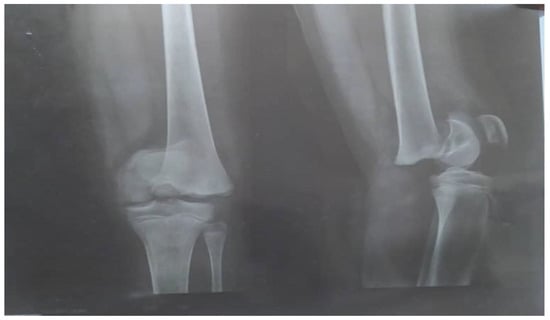

A prescription of prophylactic antibiotics with IV cefazolin, 1 g every 6 h, and pain medications (NSAIDs) was given, after which the patient was discharged home with cephalexin 500 mg tablets to be taken by mouth (PO) every 12 h for two weeks. Four weeks later, there was no improvement, and the patient returned to the hospital with fever and pain in the left knee not controlled with NSAIDs. A plain radiograph was performed, which revealed osteomyelitis of the distal left femur as shown in Figure 3.

There was also a great reduction of the hyperextended epiphysis; a lateral-based defect with a thin bridging bone anterior-medially was seen on plain X-ray images of the patient’s left knee. A percutaneous bone aspiration of synovial fluid was performed and sent to the lab for testing. The results of the culture of bone aspirate yielded a predominant of staphylococcus microbes.

Figure 3. Plain radiograph of the right and left knee with osteomyelitis (red arrows) following the insertion of percutaneous cross-pins.